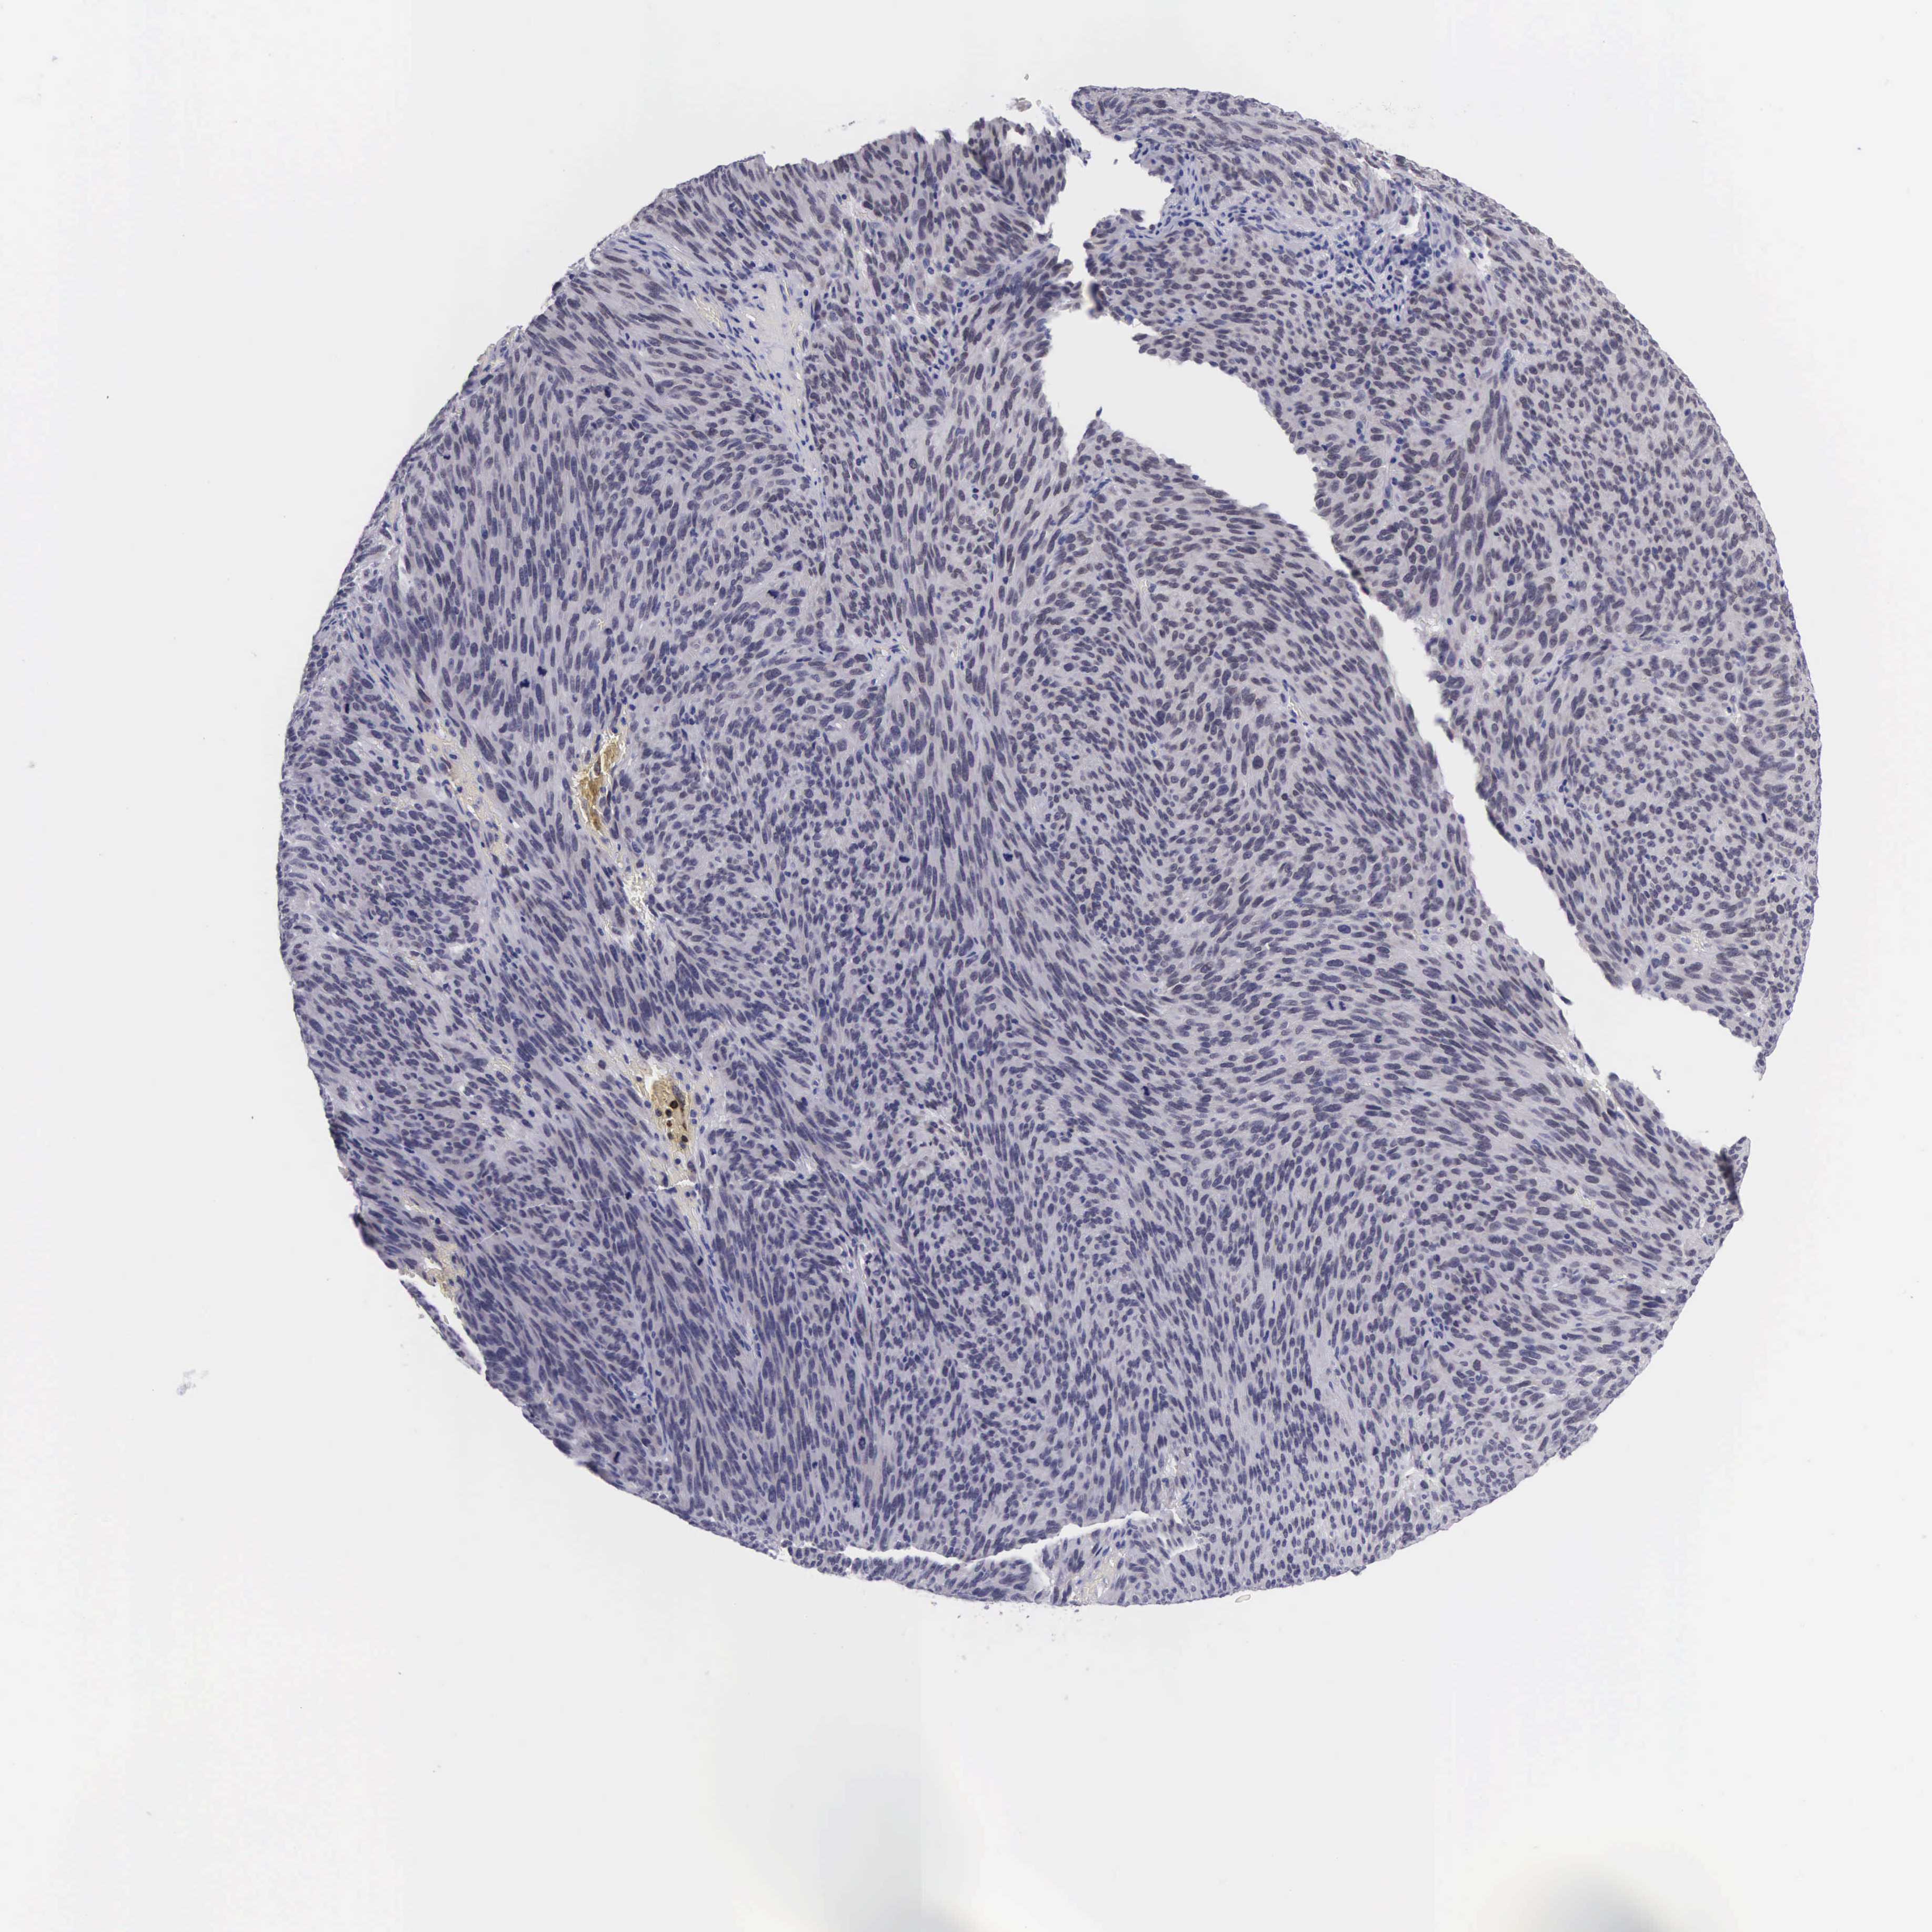

MELANOMA - Protein expressioni

A mouse-over function shows sample information and annotation data. Click on an image to view it in a full screen mode. Samples can be filtered based on level of antibody staining by selecting one or several of the following categories: high, medium, low and not detected. The assay and annotation is described here.

Note that samples used for immunohistochemistry by the Human Protein Atlas do not correspond to samples in the TCGA dataset.

Antibody stainingi

Antibody staining in the annotated cell types in the current human tissue is reported as not detected, low, medium, or high, based on conventional immunohistochemistry profiling in selected tissues. This score is based on the combination of the staining intensity and fraction of stained cells.

Each image is clickable and will lead to virtual microscopy that enables deeper exploration of all samples and also displays staining intensity scores, fraction scores and subcellular localization as well as patient and tissue information for each sample.

Antibody HPA000536

Antibody CAB056152

Antibody CAB056153

Staining

High

Medium

Low

Not detected

Intensity

Strong

Moderate

Weak

Negative

Quantity

>75%

75%-25%

<25%

None

Location

Nuclear

Cytoplasmic/membranous

Cytoplasmic/membranous,nuclear

Malignant melanoma, NOS

Malignant melanoma, Metastatic site